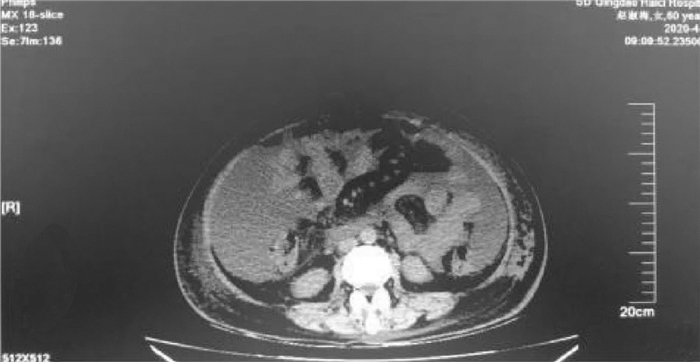

A case of decompensated liver cirrhosis complicated by abdominal necrotizing fasciitis

Guozhi WU, Xianglei ZHANG, Jia XU, Jinjun WANG, Wei LI

2021, 37(10): 2408-2410. DOI: 10.3969/j.issn.1001-5256.2021.10.030

Abstract(1184) HTML (302) PDF (2392KB)(73)

Abstract: